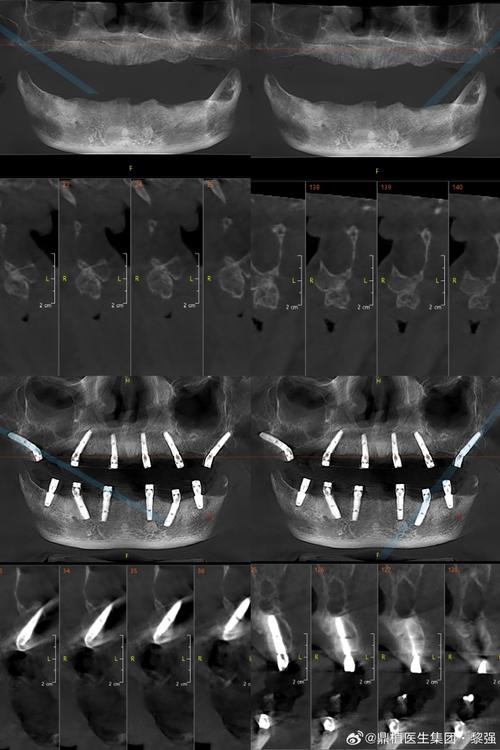

- 精确的手术计划: 需要术前进行详细的CBCT检查和数字化设计,确保种植体植入位置、角度、深度精确无误,为后期修复提供理想条件。

- 术前全面检查: 务必进行详细的口腔检查,包括CBCT(锥形束CT)扫描,评估骨量、骨密度、神经血管位置等,这是制定精准方案的基础。